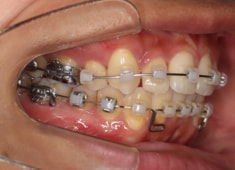

治療開始時